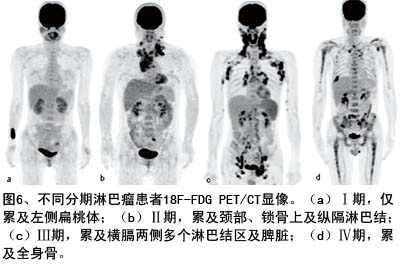

因此恶性肿瘤需要摄取大量的葡萄糖满足需要,其中就包括伪装其中的不能被细胞“消化”、又可以发射信号的18FDG,从而暴露无疑。如图所示,为不同分期淋巴瘤患者显像。